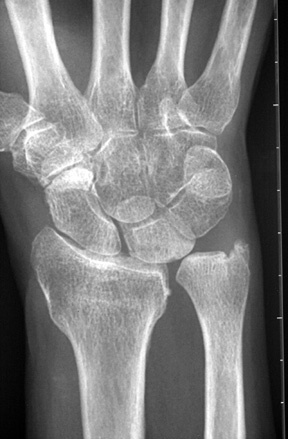

Diagnosis? Etiology?

Keinbochs

Diagnosis? Classification

Keinboch’s - Litchman Classification

Imaging to help define collapse of lunate